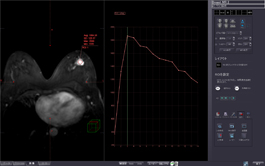

Using DCE MR images, this protocol displays high precision time-intensity curves for tissue characterization, with BI-RADS and general curve standardizations.

Analyzes blood flow using contrasted MR images scanned at the same cross-section, showing changes over time.